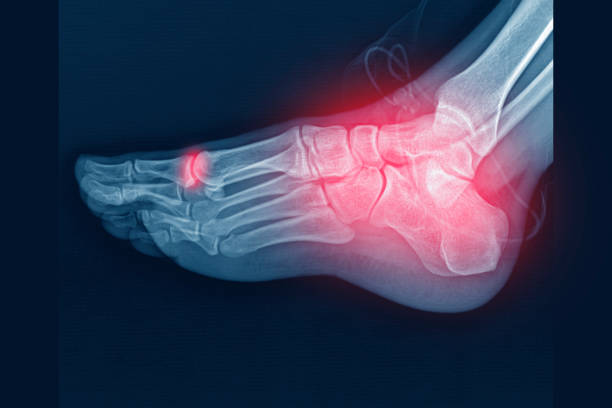

골다공증은 뼈 속에 있는 뼈가 점차적으로 없어지는 질병입니다. 이는 뼈가 흡수되어 뼈의 밀도가 감소하게 되어 발생합니다. 뼈의 밀도가 감소하면 뼈가 약해지고, 따라서 골절이 쉽게 발생할 수 있습니다. 골다공증은 주로 고령자에게서 발생하지만, 젊은 세대에서도 발병할 수 있습니다.

골다공증을 진단하려면 골밀도 검사가 필요합니다. 이 검사는 전문적인 장비를 사용하여 수행되며, 뼈의 밀도를 측정합니다. 일반적으로 혈압을 측정하는 것처럼 쉽게 이루어지지 않으며, 비용과 시간이 소요됩니다. 따라서 골다공증 진단은 다소 어려운 접근성을 가지고 있습니다.